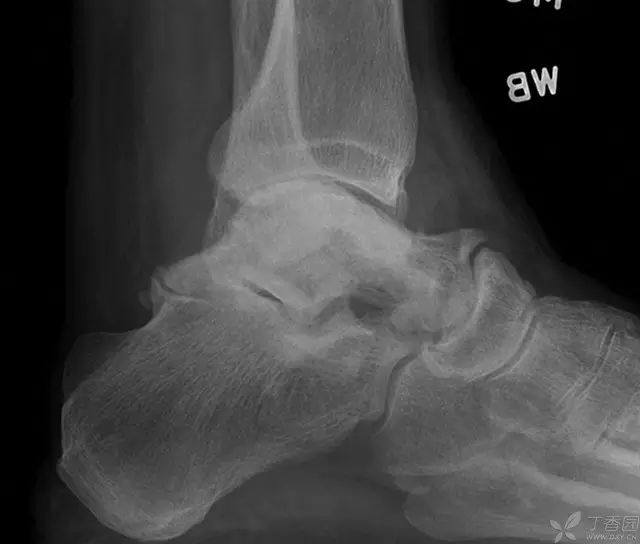

病例二[9]

33 岁男性,车祸多发伤。左踝严重污染,几乎环形创口,胫骨远端 20 cm 缺损

游离骨块生理盐水灌洗,保持湿润,4 小时内紧急手术。术中对创口和游离骨块各用 12L 生理盐水灌洗,彻底清创。外固定支架固定,创口松散地缝合

原计划 48 小时再次灌洗,因身体情况不稳定,10 天后再次进手术室清创灌洗,方法如前;48 小时后进行了第三次灌洗,然后进行了内固定,闭合创口。

3 个月后创口无感染迹象,骨折处无压痛

6 个月后,骨折线模糊,独立行走

18 个月恢复工作